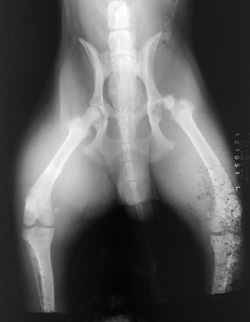

Light Fog |

Black artifact due to light on film in the dark room. The film was in its box and covered with interleafing paper. The light through the paper makes it appear as a splotchy blackening of the film. The film we use now does not have interleafing paper around it.